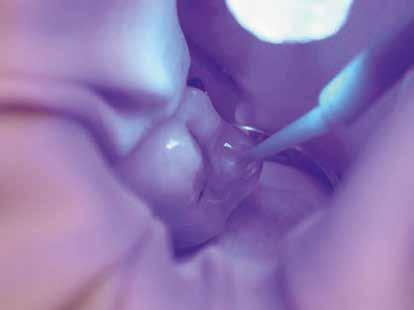

Esetbemutatás

Az alábbi cikkben egy I. osztályú üreg thermo-viszkózus kompozittal, okkluzális matrica technikával történő ellátásának lépéseit ismertetjük (1. ábra). A kofferdám felhelyezését követően az okkluzális felszín anatómiai karakterisztikáját átlátszó, folyékony, fényrekötő kompozit (Clip Flow, VOCO) segítségével rögzítettük. Az anyagot egy bondecset alkalmazásával vittük fel a fog okkluzális felszínére, majd 10 másodpercen keresztül polimerizációs lámpával megvilágítottuk (2–4. ábra). A megkötött átlátszó okkluzális matrica ellenőrzését követően (5. ábra) alkoholba helyeztük (ethanol vagy izopropil-alkohol), az oxigén inhibíciós réteg eltávolítása érdekében. Ezután a szuvas foganyagot eltávolítottuk (6–7. ábra). A zománcot 30 másodpercig, a dentint pedig 15 másodpercig savaztuk (DeTrey Conditioner 36, Dentsply Sirona), majd a felszínt levegő-vízspray segítségével lemostuk (8 –10. ábra). Mivel a fogbélkamrát már csak egy vékony réteg ép dentin fedte, ezért a pulpa vitalitásának megőrzése érdekében az üreg pulpális falait védőréteggel fedtük (DeTrey Conditioner 36, Dentsply Sirona) (11. ábra). Az adhéziót Futurabond DC (VOCO) felhasználásával biztosítottuk. A bondot bondecsettel 20 másodpercen keresztül az üreg falaiba masszíroztuk, majd 5 másodpercen keresztül olajmentes levegő spray-vel megfújtuk a felesleg eltávolítása és a bondréteg elvékonyítása érdekében. A bondot ezt követően 10 másodpercen keresztül polimerizációs lámpával megvilágítottuk (12–13. ábra). Az üreg alját nagyon vékonyan folyékony kompozitréteggel fedtük (GrandioSO Light Flow, A3.5, VOCO), amelyet 20 másodpercen keresztül polimerizációs lámpával megvilágítottuk (14–15. ábra). A bulk-fill tömőanyagot (VisCalor bulk, A2) egy olyan kézi applikátor